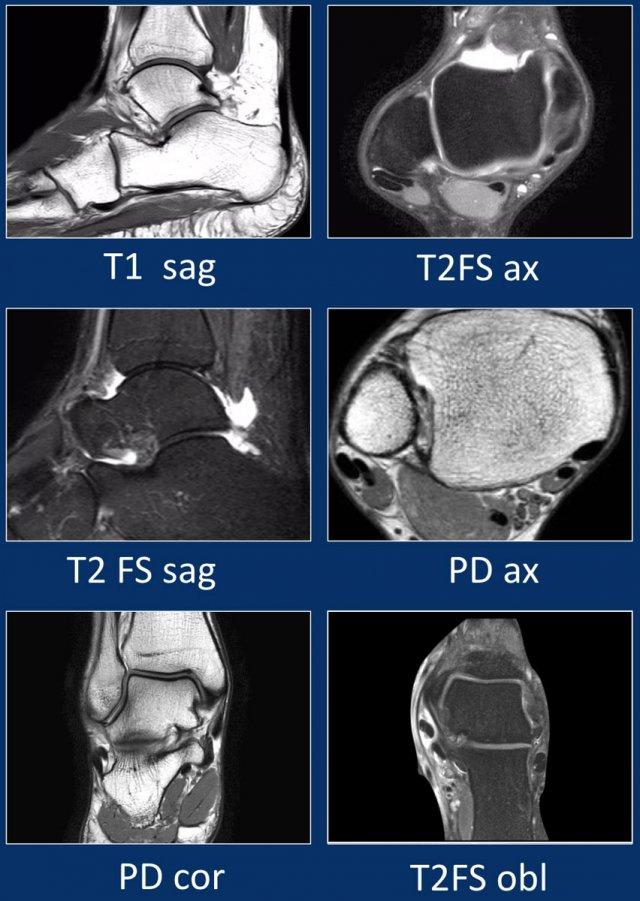

Giao thức chụp MRI

Các mặt phẳng cắt chuẩn gồm axial (ngang), coronal (trán) và sagittal (đứng dọc) được sử dụng để khảo sát khớp cổ chân trên cả máy 1,5T lẫn 3T.

Ngoài các mặt phẳng chuẩn, đôi khi bổ sung thêm mặt phẳng cắt chếch, định hướng vuông góc với các gân cơ mác và gân cơ chày sau.

Các vết rách nhỏ hoặc bệnh lý gân kín đáo sẽ được hiển thị rõ hơn trên các mặt cắt này.

Hướng đi của các gân dọc theo mắt cá trong và mắt cá ngoài có thể gây ra hiện tượng ‘xảo ảnh góc ma thuật’.

Các gân sẽ biểu hiện tín hiệu tăng tương đối khi tạo góc 55° so với B0, dễ nhầm lẫn với bệnh lý như viêm gân hoặc rách gân một phần.

Xảo ảnh này xuất hiện trên các chuỗi xung có thời gian TE ngắn (ví dụ: PD).

Trên các chuỗi xung có TE dài (như T2), xảo ảnh này cũng xuất hiện nhưng ít rõ rệt hơn.